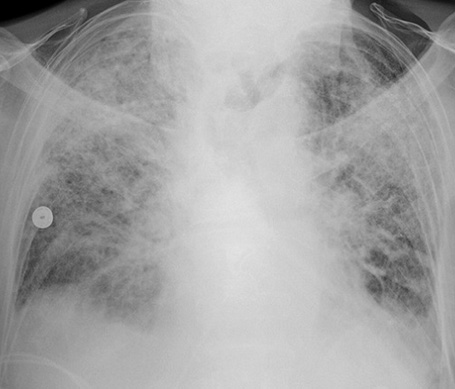

(一)肺水肿的产生 各种致病因素使肺血流灌注不足,直接损害肺泡、毛细血管上皮,引起肺泡毛细血管膜的通透性增加。血循环中的粒细胞、血小板及组织巨噬细胞释放的各种炎症介质将加重上述损害。液体及蛋白质等漏出血管外,导致肺水肿形成,影响通气/灌注比率,导致低氧血症。

(三)肺表面活性物质减少 肺表面活性物质衬附在肺泡表面.具有降低肺泡表面张力,瞅肺泡顺应性,稳定肺泡内压,防止肺毛细血管内液体渗入肺泡内的功能。它由厦型肺泡上皮细胞的线粒体合成及分泌的,其主要成分为二棕悯酮亚磷脂,大约18—24小时更新一次。 急性呼吸窘迫综合征发病时,由于上述肺小血管痉挛及肺微小血管栓塞所致的肺血流减少,影响h型肺泡上皮细胞代谢,磷脂合成发生障碍;或由于水肿液、脂肪酸、氧个毒等因素直接破坏作用,使肺表面活性物质减少,表面张力增高,肺泡缩小、陷闭,形成肺不张,同时肺毛细血管内液体渗入肺间质及肺泡。